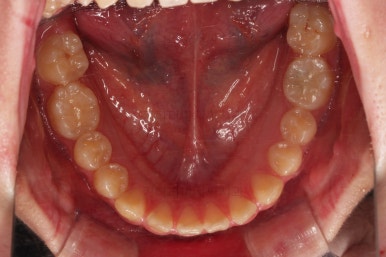

틈이 다 모였고 교합도 많이 좋아졌죠?

끝내도 될까요?

안정성을 충분히 확인한 뒤 치료를 종료합니다.

틈새가 벌어지더라도 뒤쪽에 벌어지라고 앞니쪽은 유지철사를 부착하고요.

전후 사진을 비교해 볼게요.

악궁확장을 통해 위아래 악궁의 크기 조화를 맞췄고, 틈새도 모았으며 교합도 적절히 마무리를 했습니다.